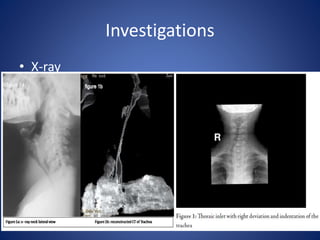

Radiological investigations

Normal AP and lateral

chest X-rays may

demonstrate

retrosternal extension

of the goiter

(retrosternal shadow)

Thoracic inlet X-rays

may demonstrate

compression or

deviation of the

trachea, this

important to

anesthetist if surgery

is contemplated

(difficult intubation).